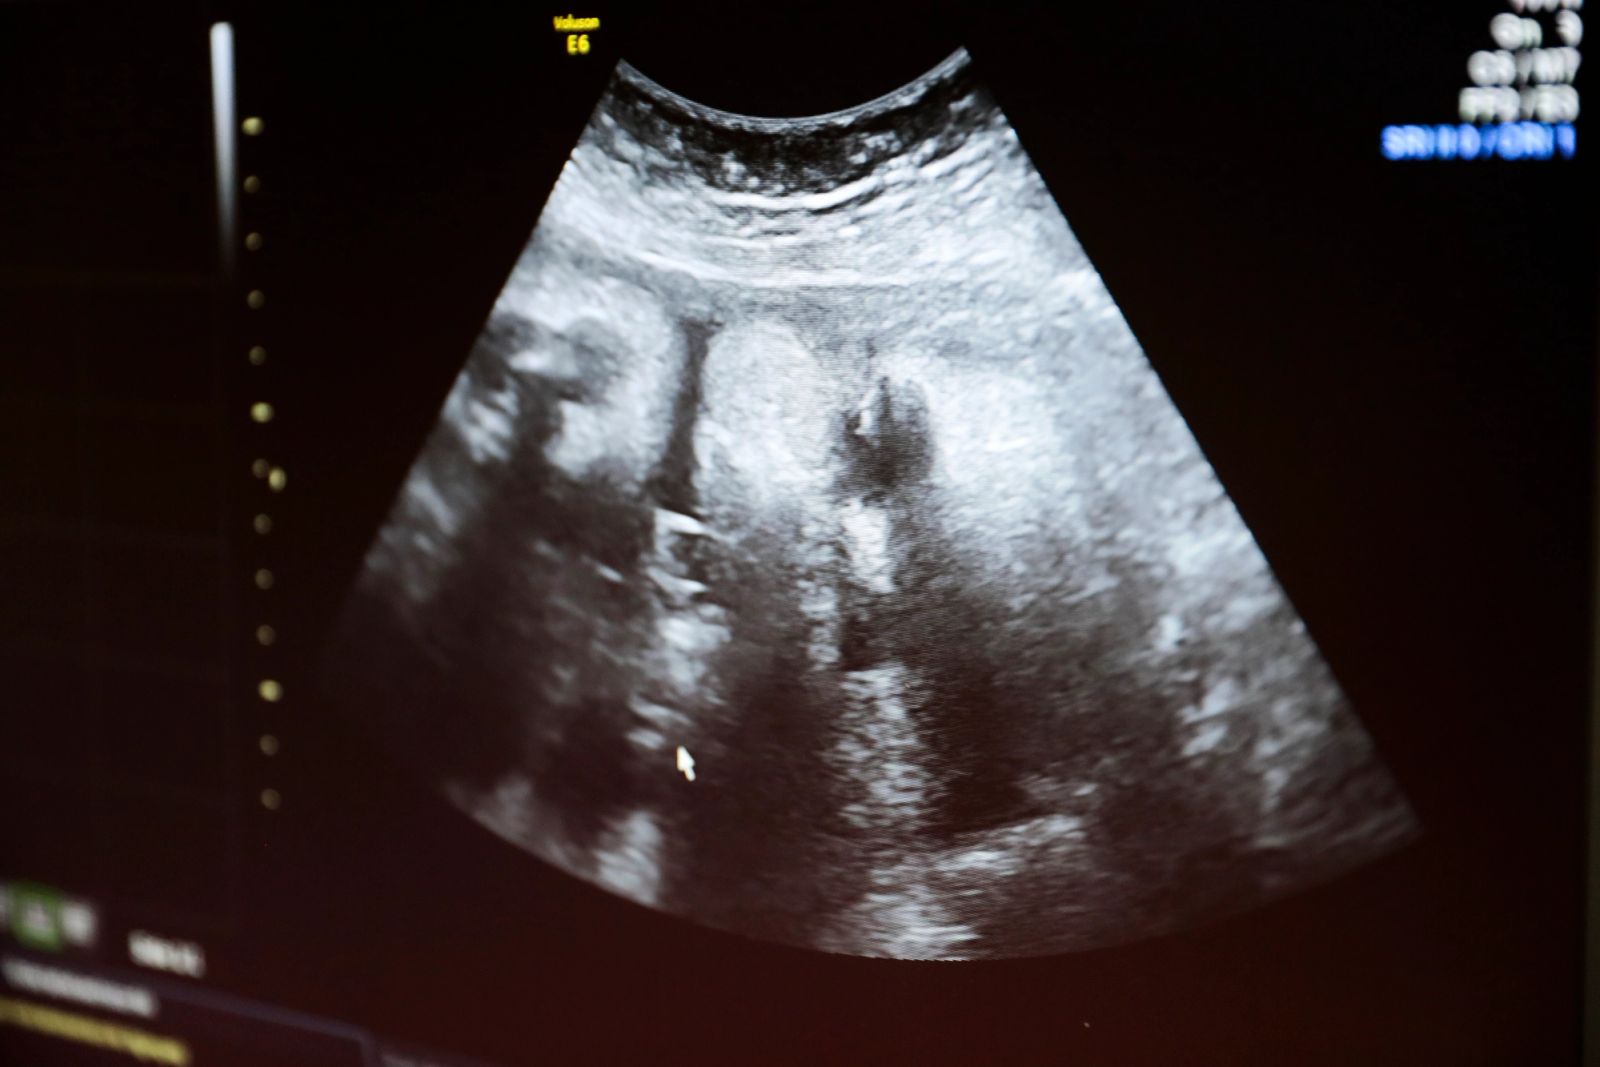

Hun sang for seg selv: «Mitt liv, min kropp, ja til selvbestemt abort.» Vi hadde vært i 8. mars-tog – som hvert eneste år, foruten det året jeg hadde termin på kvinnedagen med hennes bror. Det har jeg gjort fordi jeg vil hun tidlig skal flaskes opp på feminismen. Men jeg følte også hun burde skjønne hva hun gjentok. Så jeg sa: «Du vet hva det betyr? At det er viktig at damer som ikke vil ha barn får gå til legen og ta bort barnet i magen, så de ikke skader seg hvis de må gjøre det selv.» Jeg visste jeg var på dypt vann når hun snudde seg: «En mamma som tar bort barnet i magen?» Ja, sa jeg, men det er egentlig ikke et barn: «De gjør det så tidlig, lenge før det har blitt et barn.»